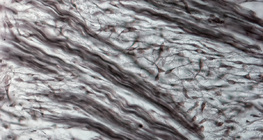

200 дахин томруулсан